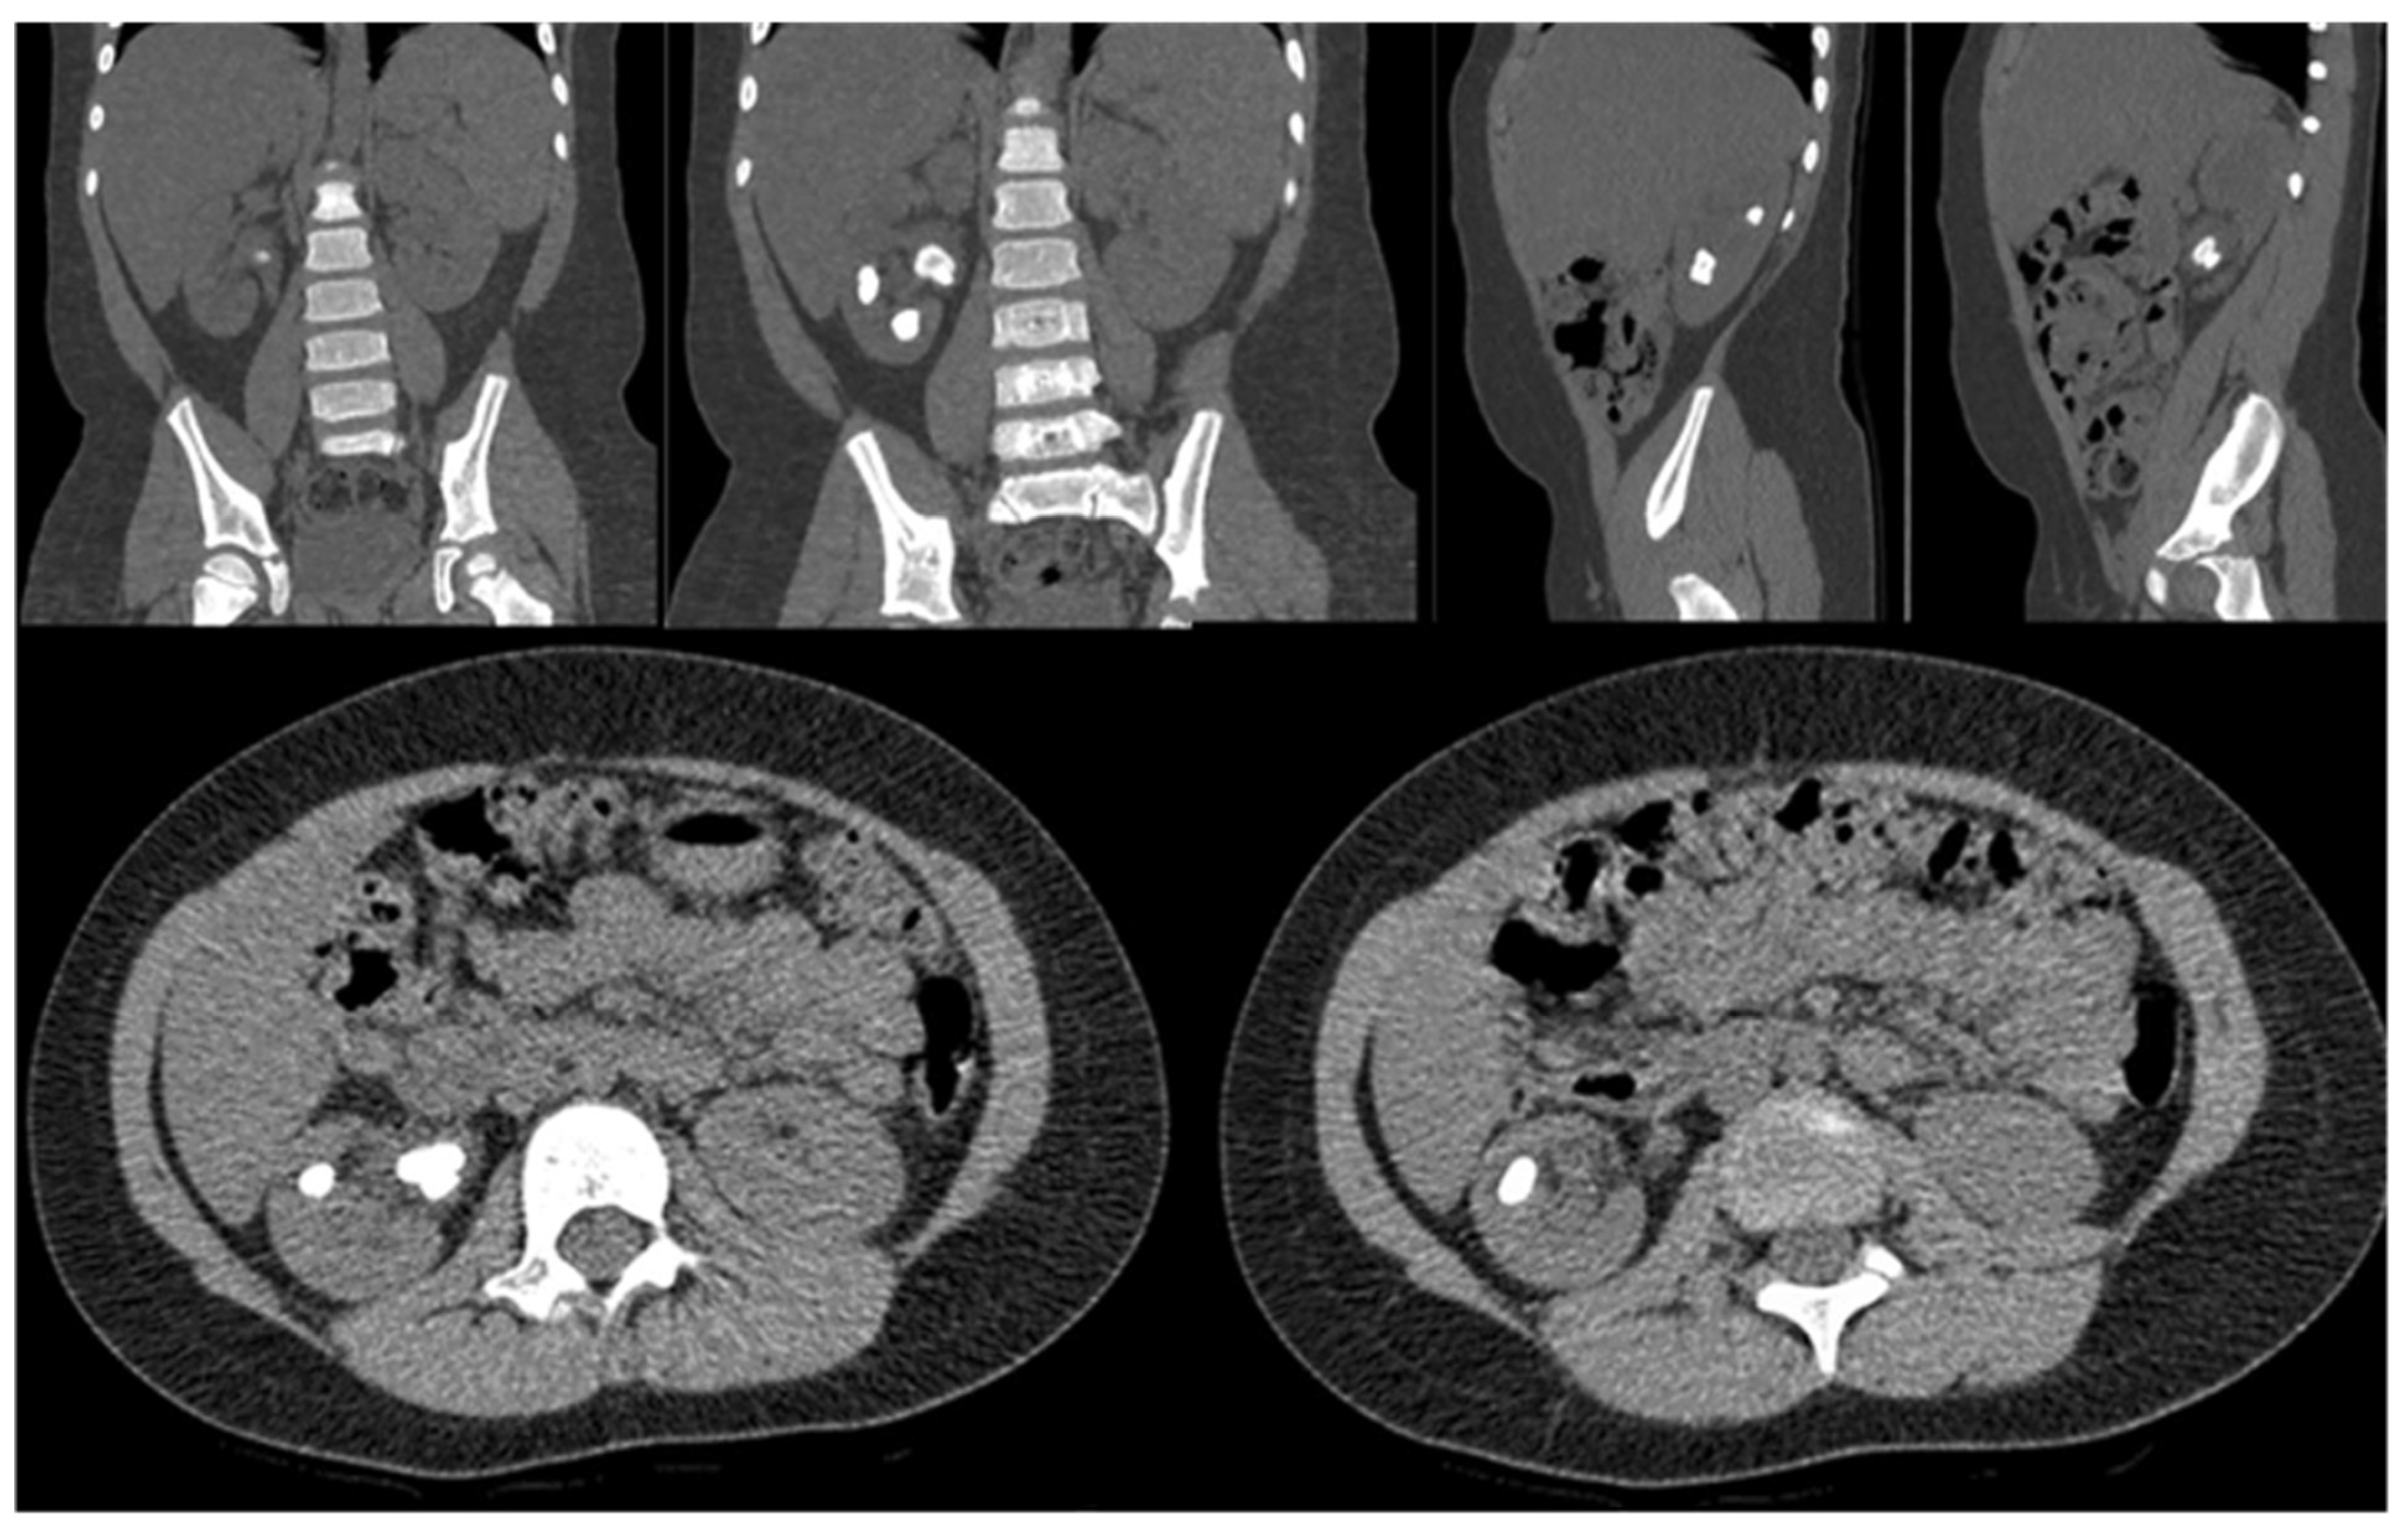

In the two patients in whom the presence of renal stones had been detected by ultrasonography, an abdominal CT (Figure 1) was performed to better define nephrolithiasis.

Figure 1.

Abdominal CT scan showing right nephrolithiasis in a kidney affected by right UPJO.